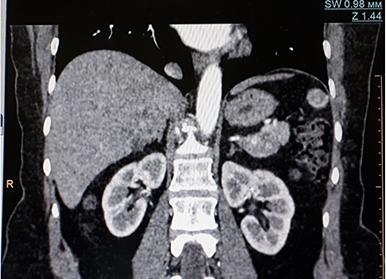

Кт забрюшинного пространства

КТ забрюшинного пространства — это метод исследования тканей с использованием рентгеновских лучей, при котором доктор получает послойное изображение нужных органов в заданной плоскости. Высокая точность и информативность этого метода исследования позволяет с большой вероятностью поставить верный диагноз и составить правильную схему лечения.